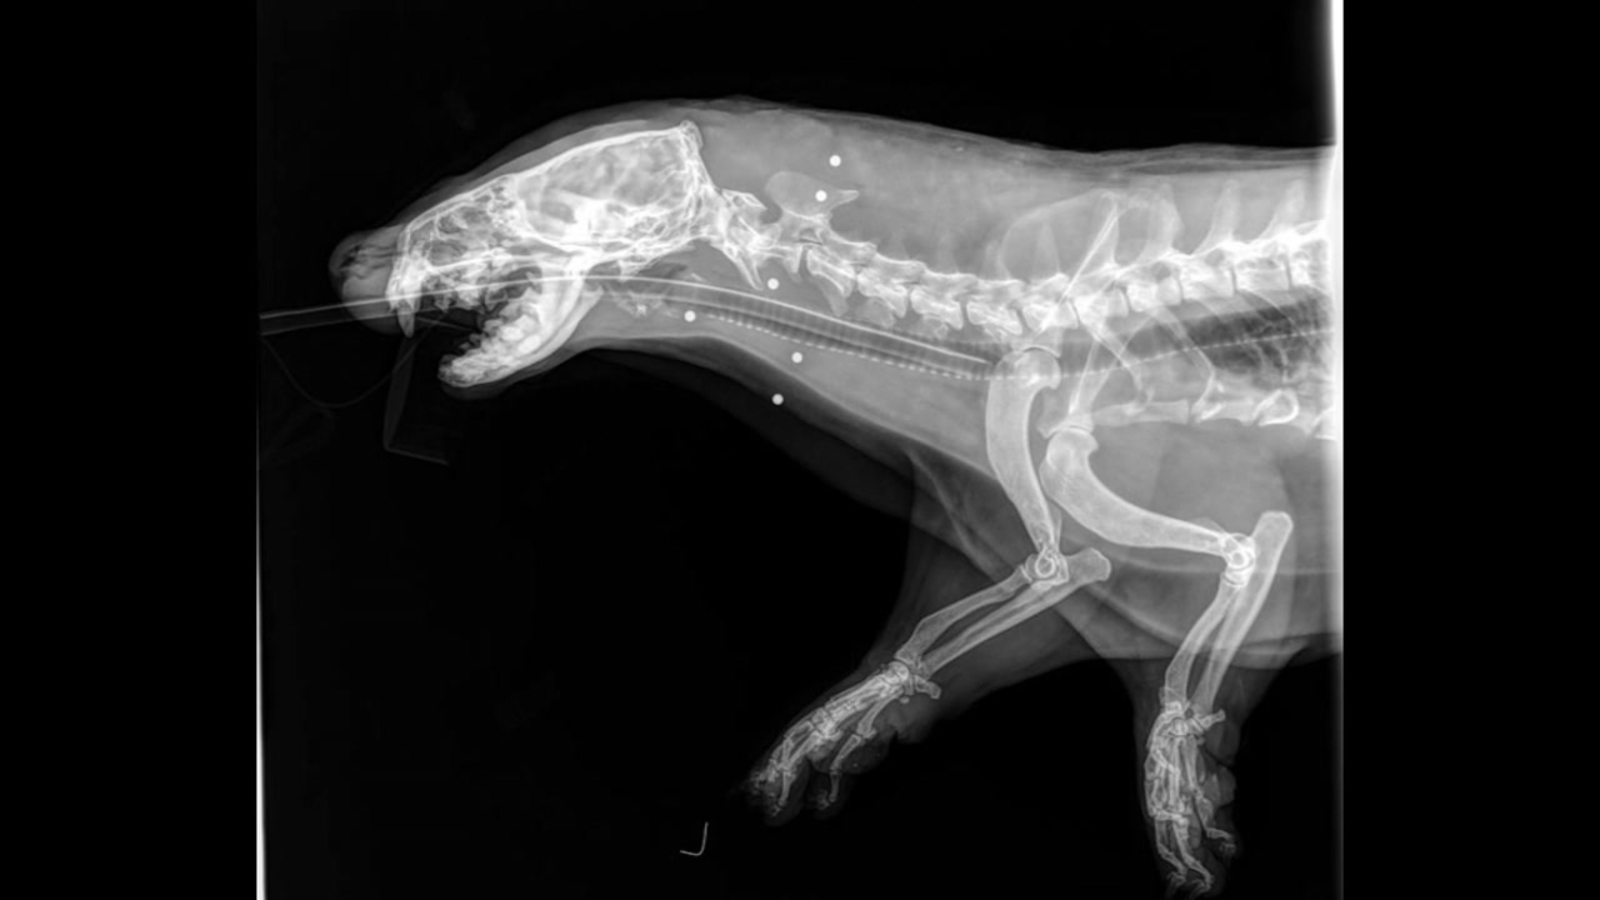

X-rays show pellets lodged in the otter's head and neck.

Veterinarians say the otter was blind and lost teeth because of being shot.